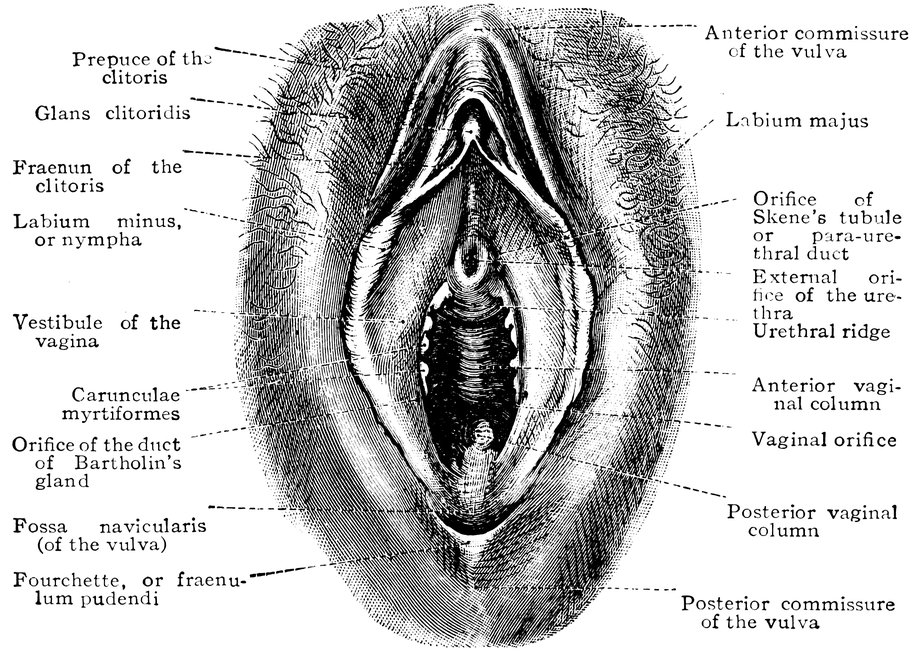

| 49. | Vestibule of the vagina, with the labia minora or nymphæ, etc | 205 |

| 51. | Female internal genital organs in the fully developed state | 208 |